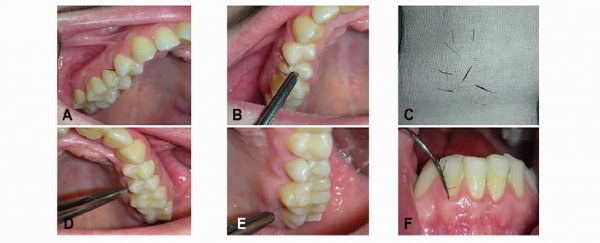

وبمعنى أوضح، وجدوا مجموعة من الشعرات، التي تشبه الرموش، تخرج من الأنسجة الرخوة خلف الأسنان الأمامية العلوية مباشرة.

وأُزيلت الشعرات جراحيا، وتناولت الشابة عقارا للمساعدة في معالجة الخلل الهرموني، وأصبح فمها خاليا من الشعرات المزعجة، لفترة من الوقت على الأقل.

وهذه المرة، لم يقم الفريق الطبي بإزالة الشعر فقط، واغتنموا الفرصة لأخذ جزء صغير من الأنسجة لإلقاء نظرة فاحصة تحت المجهر، ليجدوا أن الشعر يمتد من خلال أنسجة كثيفة غير معتادة في اللثة.